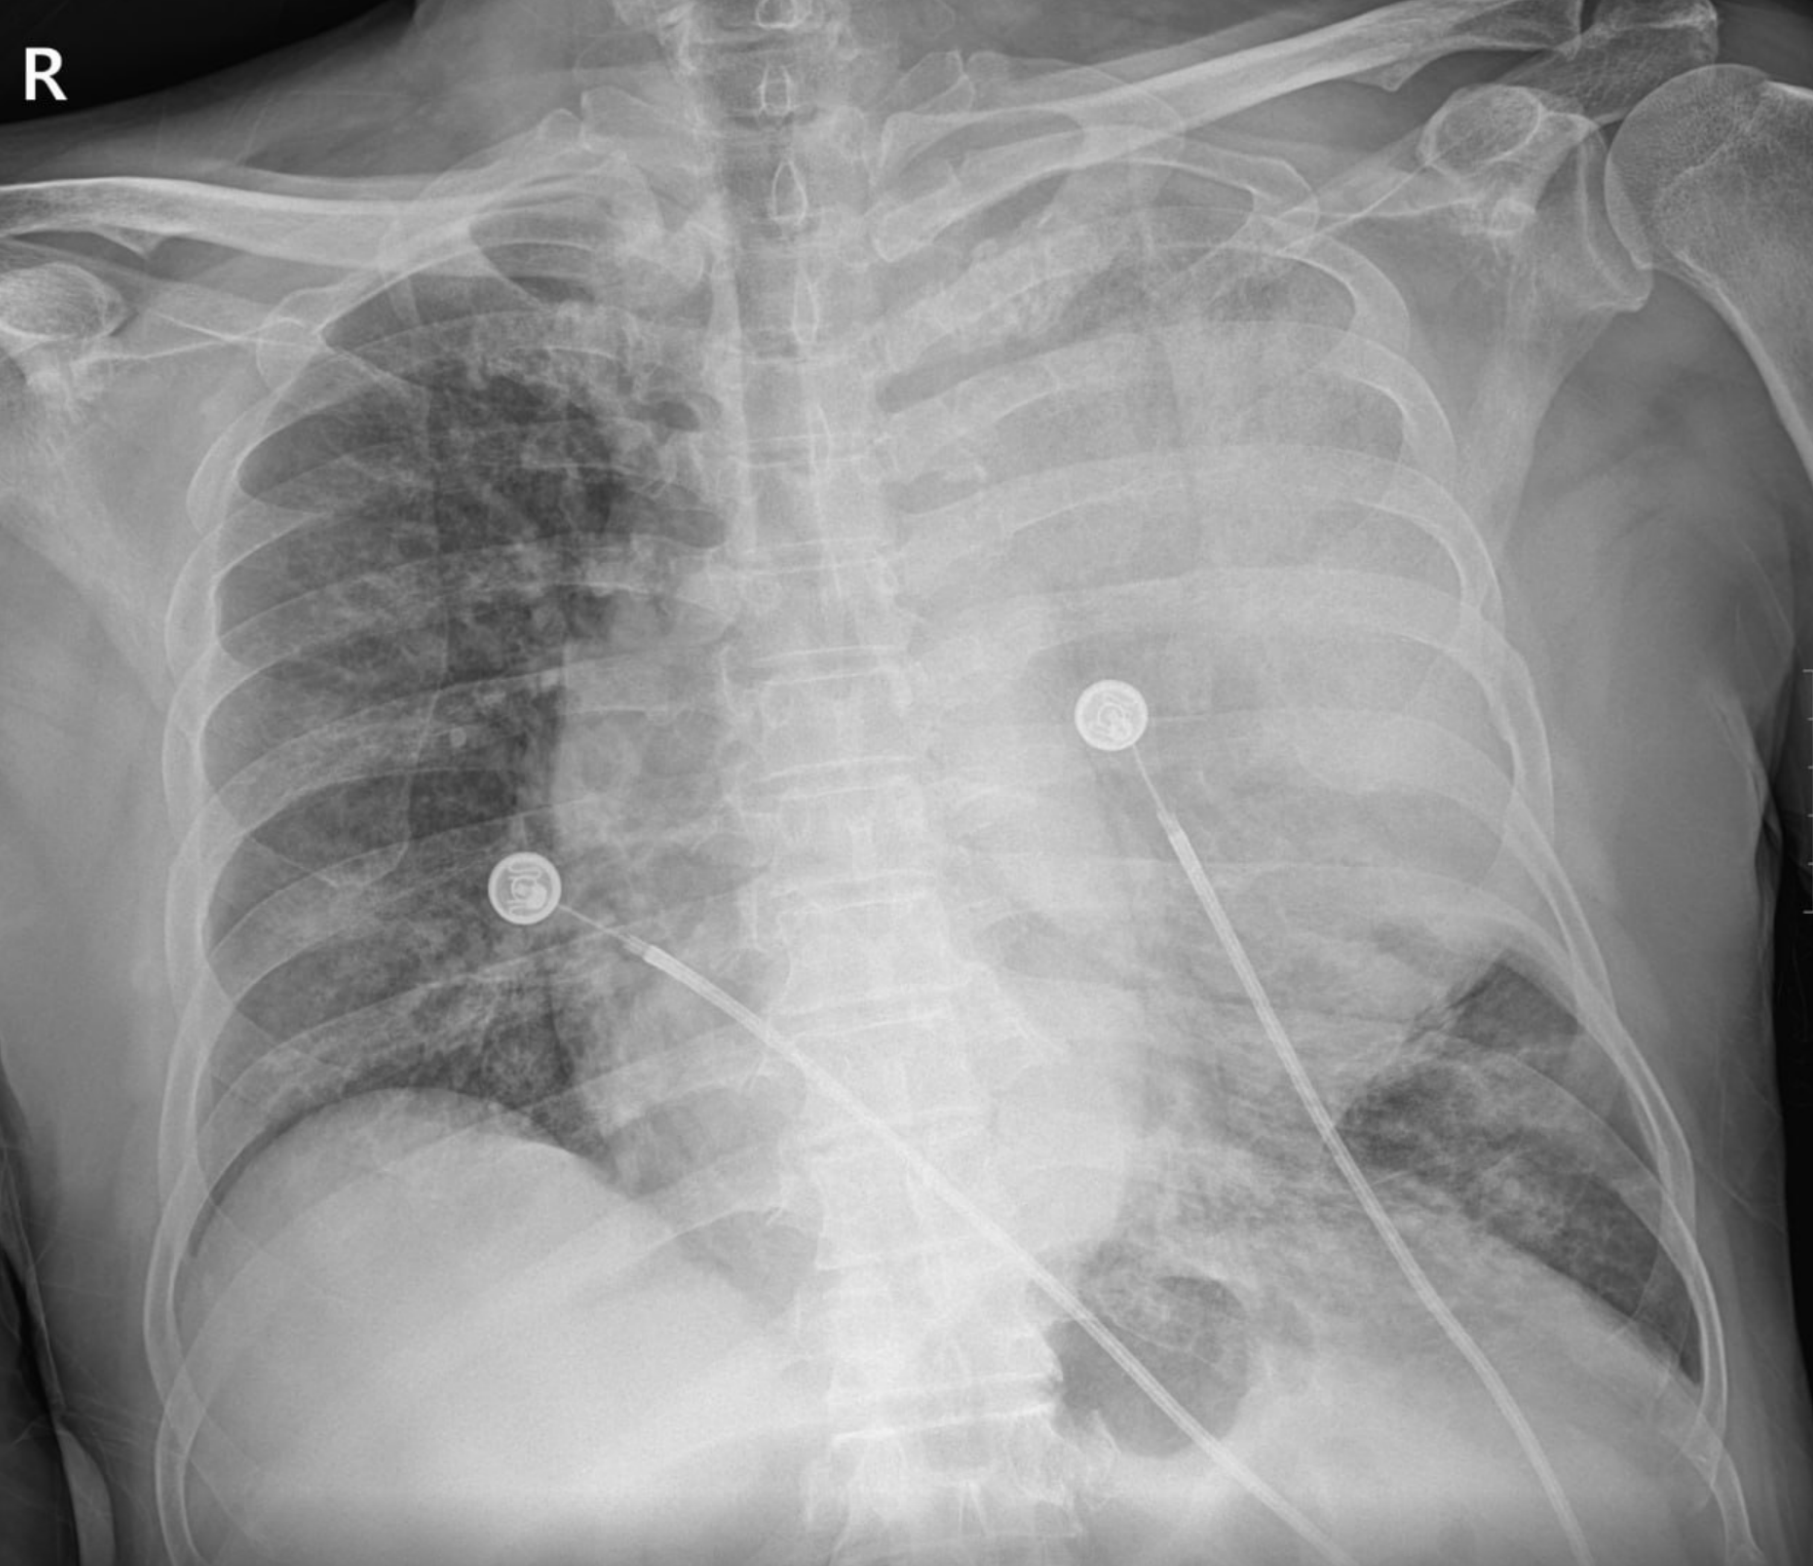

hematemsis(119) -> hemoptysis 로 판명 (L tube clear)

Result)

Expire